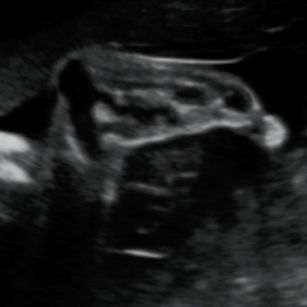

Position

Some babies may begin moving into a head-down position, but many still change positions frequently at this stage.